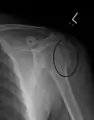

Humerus fracture

| Midshaft humerus fracture with callus formation | |